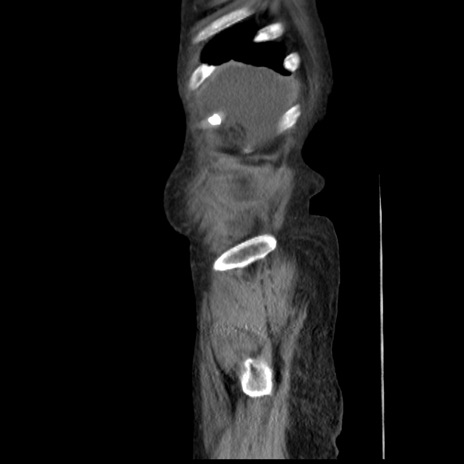

症例31(矢状断像)

【症例】80歳代 女性

【主訴】腹部膨満感

【現病歴】他院にて肝硬変にてフォロー中。1週間前から便秘、腹部膨満感、臍部腫瘤あり受診となる。

【既往歴】肝硬変

【身体所見】腹部膨隆あり、皮膚変化なし、疼痛なし。

【データ】WBC 4600、CRP 0.25